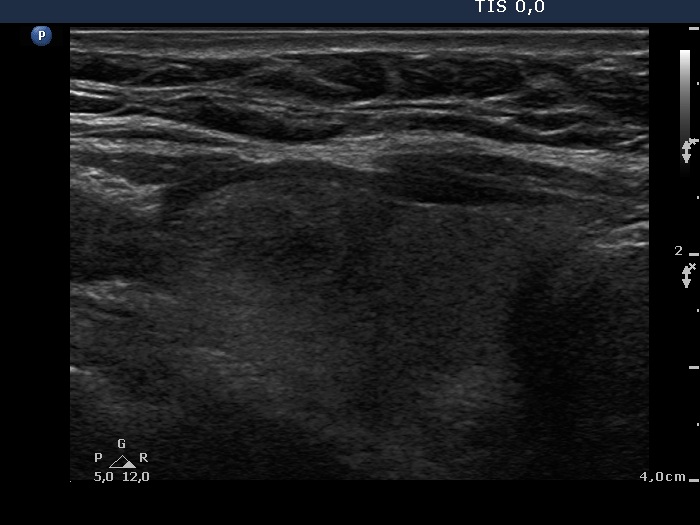

The role of complex diagnosis - follow-up of follicular lesions - Case 9.

4 years after initial investigation (ultrasonographic picture 2)

Right lobe, longitudinal scan.